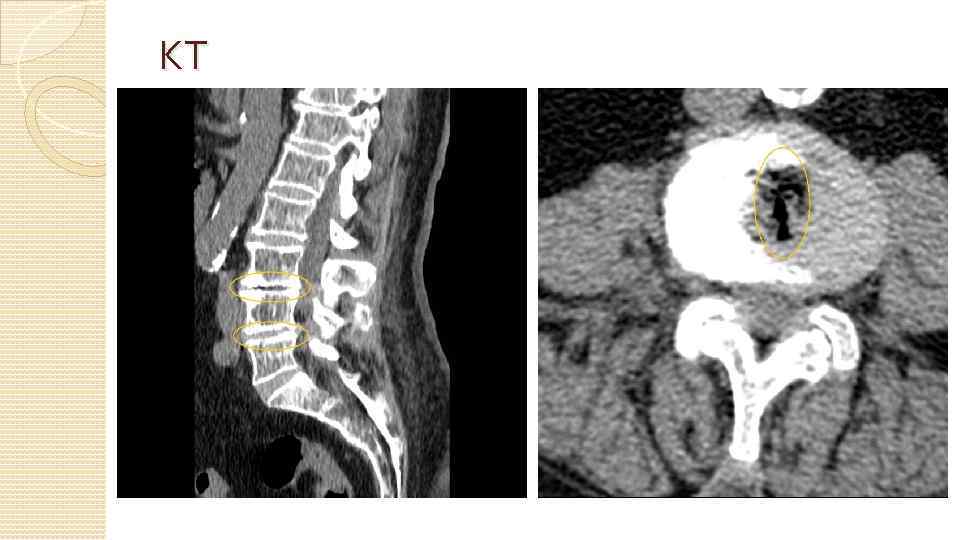

Методы диагностики Сбор анамнеза, жалоб Неврологическое обследование Рентгенография КТ МРТ Электронейромиография (ЭНМГ) ЭКГ, УЗИ БЦА, УЗИ органов брюшной полости и малого таза, ФГДС и др.

КТ